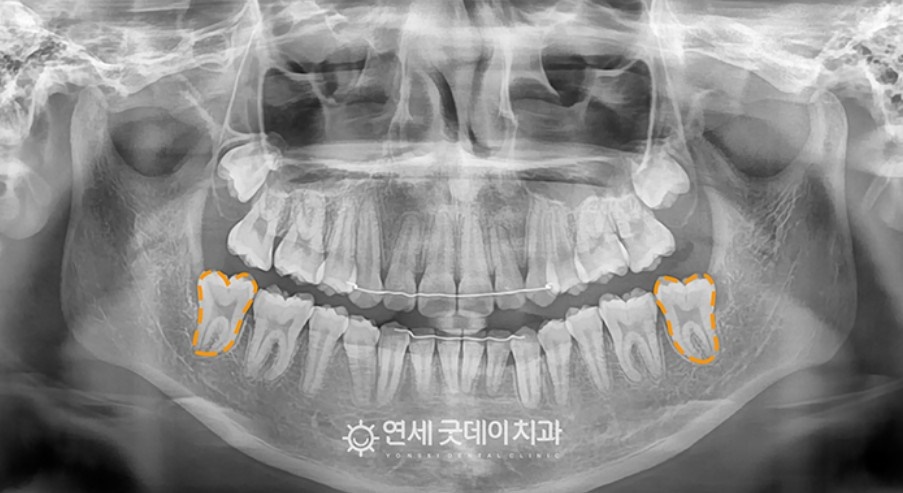

Before & After

전과 후를 비교함으로서 삐뚤어져 있던 덧니와 치아중심선이 바로잡힌 모습이 더 잘 보입니다.

매복치아 부분도 예쁘게 해결되었습니다.

엑스레이상으로 그 차이를 뚜렷하게 볼 수 있으며 치료 이후로도 교합이나 기능적으로도 잘 쓰고 있는 것을 확인할 수 있었습니다.

처음 환자분은 심각하게 누워있는 치아를 보고 체념했지만 치료결과를 통해 만족할 수 있다고 말씀해 주셔서 저희도 같이 뿌듯해지던 순간이었습니다. 이처럼 적절한 시기에 치료하여 제 위치를 찾는다면 매복치였더라도 다른 치아와 같이 사용할 수 있습니다.